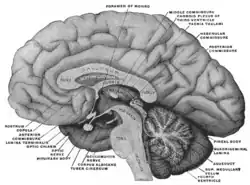

Diagrama de um corte sagital mediano através da hipófise de um macaco adulto. | |

Do ponto de vista fisiológico, a hipófise é dividida anatomicamente e funcionalmente em duas partes distintas: o lobo anterior (adeno-hipófise) e o lobo posterior (neuro-hipófise). A adeno-hipófise possui origem de células epiteliais, enquanto neuro - hipófise possui origem nervosa. Entre essas duas porções existe uma zona pouco vascularizada chamada de parte intermédia, praticamente ausente em humanos, mas bem desenvolvida e funcional em outros animais.[2]

Embriologia: durante o processo de formação na vida embrionária, observa-se que a parte distal e a parte intermediaria se originam da bolsa de Rathke (originada do teto da cavidade oral do embrião, ectoderma, o estomodeu) e que a parte nervosa se origina de uma invaginação do assoalho do terceiro ventrículo. Em seguida, as duas partes se aproximam e formam uma glândula aparentemente única.[1] Como remanescente deste desenvolvimento embriológico, observamos a presença de folículos entre neurohipófise e adenohipófise, cuja função é ainda desconhecida.

Hipófise posterior (neuro-hipófise)

O lobo posterior é conectado à parte do cérebro chamada de hipotálamo através do infundíbulo. A neurohipófise não produz nenhum hormônio apenas armazena os secretados pelo hipotálamo, e estes hormônios são então transportados pelos axônios das células nervosas em direção à hipófise posterior.

Hipófise anterior (Adeno - hipófise)

O lado anterior é derivado do ectoderma oral e é composto de epitélio glandular. Através da conexão vascular da hipófise anterior com o hipotálamo, o hipotálamo integra sinais estimulatórios e inibitórios centrais e periféricos para os cinco tipos fenotipicamente distintos de células da hipófise.

Sistema Porta-Hipofisário

As secreções da hipófise são controladas por sinais hormonais ou nervosos provenientes do hipotálamo. A secreção do lobo posterior da hipófise é controlada por sinais nervosos que se originam no hipotálamo e terminam na neuro - hipófise. Em contraste, pois a secreção pelo lobo anterior da hipófise é controlada por hormônios denominados hormônios ou fatores hipotalâmicos de liberação ou inibição secretados pelo próprio hipotálamo e, posteriormente, transportados até a adeno - hipófise por meio de pequenos vasos sanguíneos, conhecidos como vasos porta hipotalâmicos - hipofisários. Na adeno- hipófise, esses hormônios de liberação e inibição atuam sobre as células glandulares, controlando sua secreção.

O sistema porta hipotalâmico hipofisário é constituído por pequenos vasos comuns à extremidade inferior do hipotálamo e á hipófise anterior, unidos através do infundíbulo. Neurônios especias, situados no hipotálamo, sintetizam e secretam os hormônios hipotalâmicos liberados e inibidores. A função desses hormônios é a de controlar a secreção dos hormônios da hipófise anterior. O hipotálamo recebe sinais de quase todas as fontes possíveis do sistema nervoso. Por conseguinte, o hipotálamo é um centro coletor da informação, relacionada com o bem - estar interno do organismo; por sua vez, grande parte dessa informação é utilizada no controle das secreções dos numerosos hormônios hipofisários importantes.